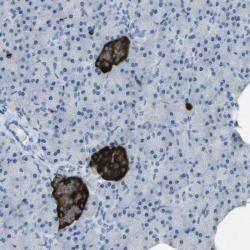

- Experimental details

- Immunohistochemical staining of human pancreas shows distinct cytoplasmic positivity in islet cells.

- Validation comment

- Staining pattern partly consistent with experimental and/or bioinformatic data.